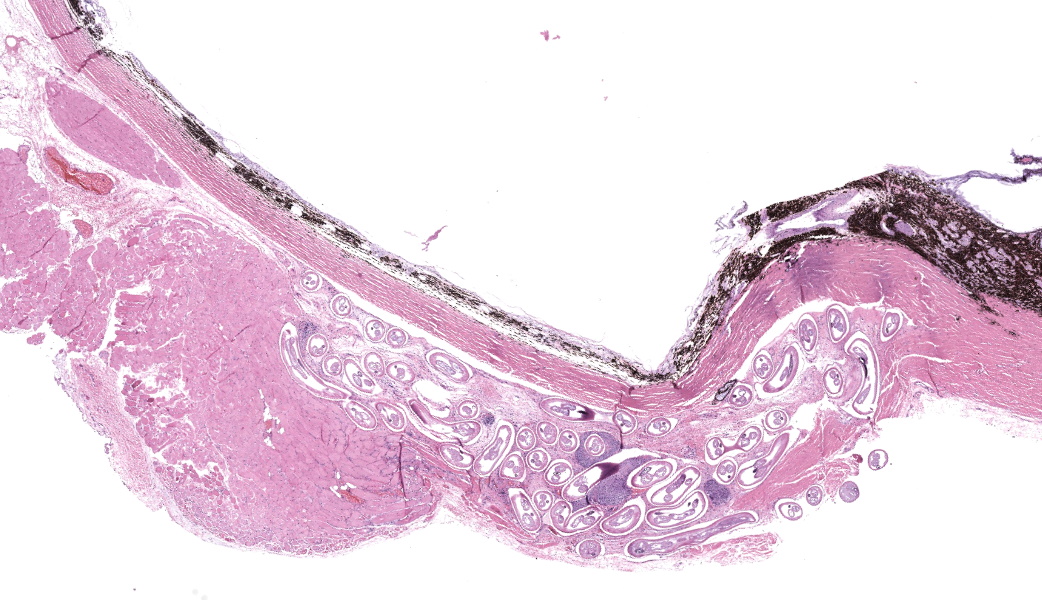

Enucleated right eye: Expanding and infiltrating the sclera, and occasionally extending to and dissecting the periocular skeletal muscle, are multiple cross and oblique sections of nematode parasites. Nematodes are characterized by a thick cuticle with annular ridges seen as raised areas in oblique sections, coelomyarian/polymyarian musculature that is atrophied and multifocally replaced by hypodermal tissue, a very small intestinal cross section, and reproductive organs. Mild hemorrhage, fibrin, and edema are present in affected sclera, and occasional nematode cross sections are surrounded by epithelioid macrophages. The cornea is hypercellular with low numbers of neutrophils and areas of neovascularization.Contributor's Morphologic Diagnoses:

Clinically, canine cases of Onchocerca lupi may present with single or multiple, variably sized nodules on the bulbar conjunctiva, conjunctival hyperemia, episcleral injection, chemosis, periocular swelling, retinal detachment, and corneal edema.13,14 Typical gross lesions include nodules affecting the conjunctiva, episcleral tissue, and periorbital soft tissues.13 Some cases do not have reported clinical signs directly attributable to Onchocerciasis, and are diagnosed as an incidental lesion on biopsy secondary to other presenting causes like neoplasia.13 Bilateral involvement is described.14

Onchocerca lupi is typically diagnosed via histopathology, and to our knowledge no commercially available polymerase chain reaction (PCR) tests is available, although PCR assays have been described in the peer reviewed literature.7,14 Typical histologic lesions include nematodes with very small intestinal cross sections, atrophied coelomyarian/polymyarian musculature, and annular cuticular ridges that can be seen in longitudinal or oblique sections. Microfilaria may be seen within female worms. Variable amounts of inflammation ranging from mild to severe, and including macrophages, lymphocytes, and eosinophils may be seen, as can fibroplasia. We have seen pyogranulomatous inflammation as well in our laboratory. Currently, a commercially available serology test is not available, although serologic tests are in development.15

- Globe and periocular tissue: Scleritis and orbital rhabdomyositis, granulomatous, chronic, multifocal, moderate, with adult filarids.

This third case stimulated excellent discourse on ocular pathology and the associated changes seen in this eye. While the nematodes in the periocular tissues were striking, the other ocular lesions were a point of discussion focus for conference participants to ensure residents in attendance understood the importance of not getting “pigeon-holed” onto one lesion before examining the tissues in their entirety. This eye had multiple other lesions, some of which were subtle, and these caught the attention of the more experienced participants in the room. The keratitis in this eye served as a springboard to discuss the other changes, and conference participants suspect the keratitis was secondary to melanosis and inflammation causing occlusion of the drainage angle in this case, resulting in secondary glaucoma (as evidenced by degeneration of inner retinal cells and retinal ganglion cell loss) and subsequent buphthalmia. One of the more common sequelae to buphthalmia is an exposure keratitis due to inability of the eyelids to completely close over the enlarged eye. Coupled with possible irritation from the nematodes, participants felt that the keratitis and precluding factors were important features to discuss in this case.Conference participants unanimously agreed that the nematodes in section were consistent with Onchocerca lupi. For the sake of educational discussion, differentials for ocular nematodes in a dog were: Toxacara canis (ascarid), Onchocerca lupi (spirurid), Angiostrongylus vasorum (metastrongylid), Dirofilaria immitis (spirurid), Ancylostoma caninum (strongylid), Trichinella spiralis (aphasmid), and Thelazia spp. (spirurids). Of these, Thelazia spp. are the true ocular parasite and tend to reside in the conjunctival sacs and lacrimal ducts of infected animals. Onchocerca spp. in other species were briefly discussed, and honorable mentions included O. cervicalis, which sets up shop in the nuchal ligament of horses, O. gutturosa and O. lienalis, both of which invade the nuchal and gastrosplenic ligaments of cattle, and O. volvulus, the causative agent of “river blindness” in humans.